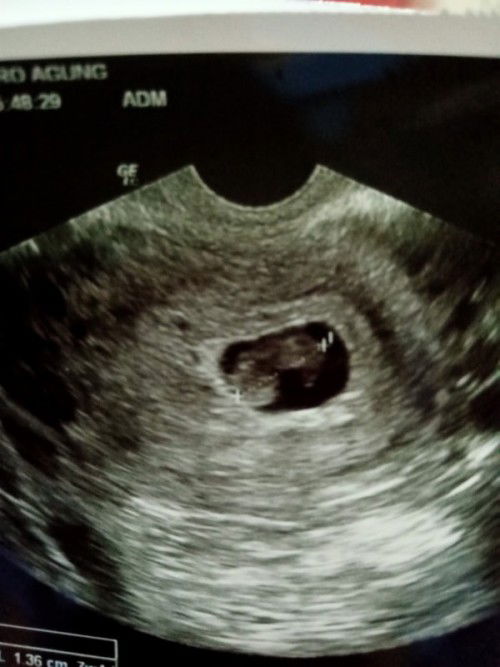

Waktu 1 hari pendarahan di sertai nyeri dari jalan lair sekali itu lgsng periksa ke obgyn. Dan mens ku TDK teratur JD blm tau brp week kehamilan. Di USG belum terlihat apa2. Tapi tespek udah nunjukin garis 2 tegas. Mungkin bari 4weekan . Di kasih dokter pregnabion dan nonemi. Adakah di sini yg flek sampai berhari2 tapi janin normal2 saja ? Dan yg di rasain apa aja ? #pleasehelp Saya takut .. #bantusharing #seriusnanya #ingintahu

Hari ini keluar flek belum tau hamil brp week